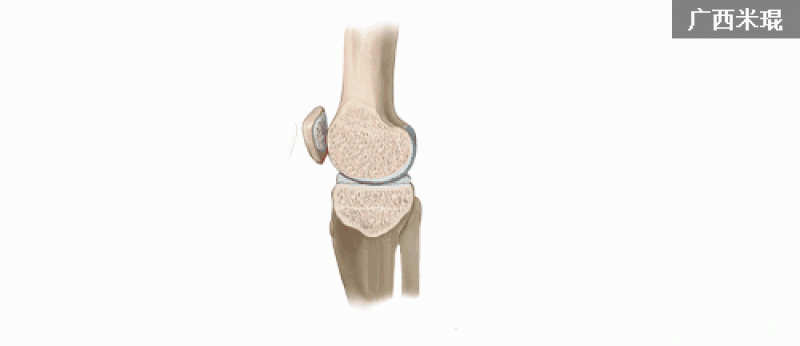

5.髌骨脱位(patellar dislocation)

髌骨脱位是一种常见的损伤,其损伤是短暂性的,病人不一定意识到,而在体检时由于肿胀和疼痛而影响检查,因此有50%-70%的患者在初次就诊时不能获得诊断。

髌骨脱位是髌骨内侧与股骨外髁外侧壁发生撞击,在MRI上主要表现为髌骨内侧及股骨外髁外侧壁的骨髓水肿,T2WI及STIR像呈高信号改变。可合并内侧髌股副韧带撕裂、髌骨及其股骨外髁的骨软骨损伤。